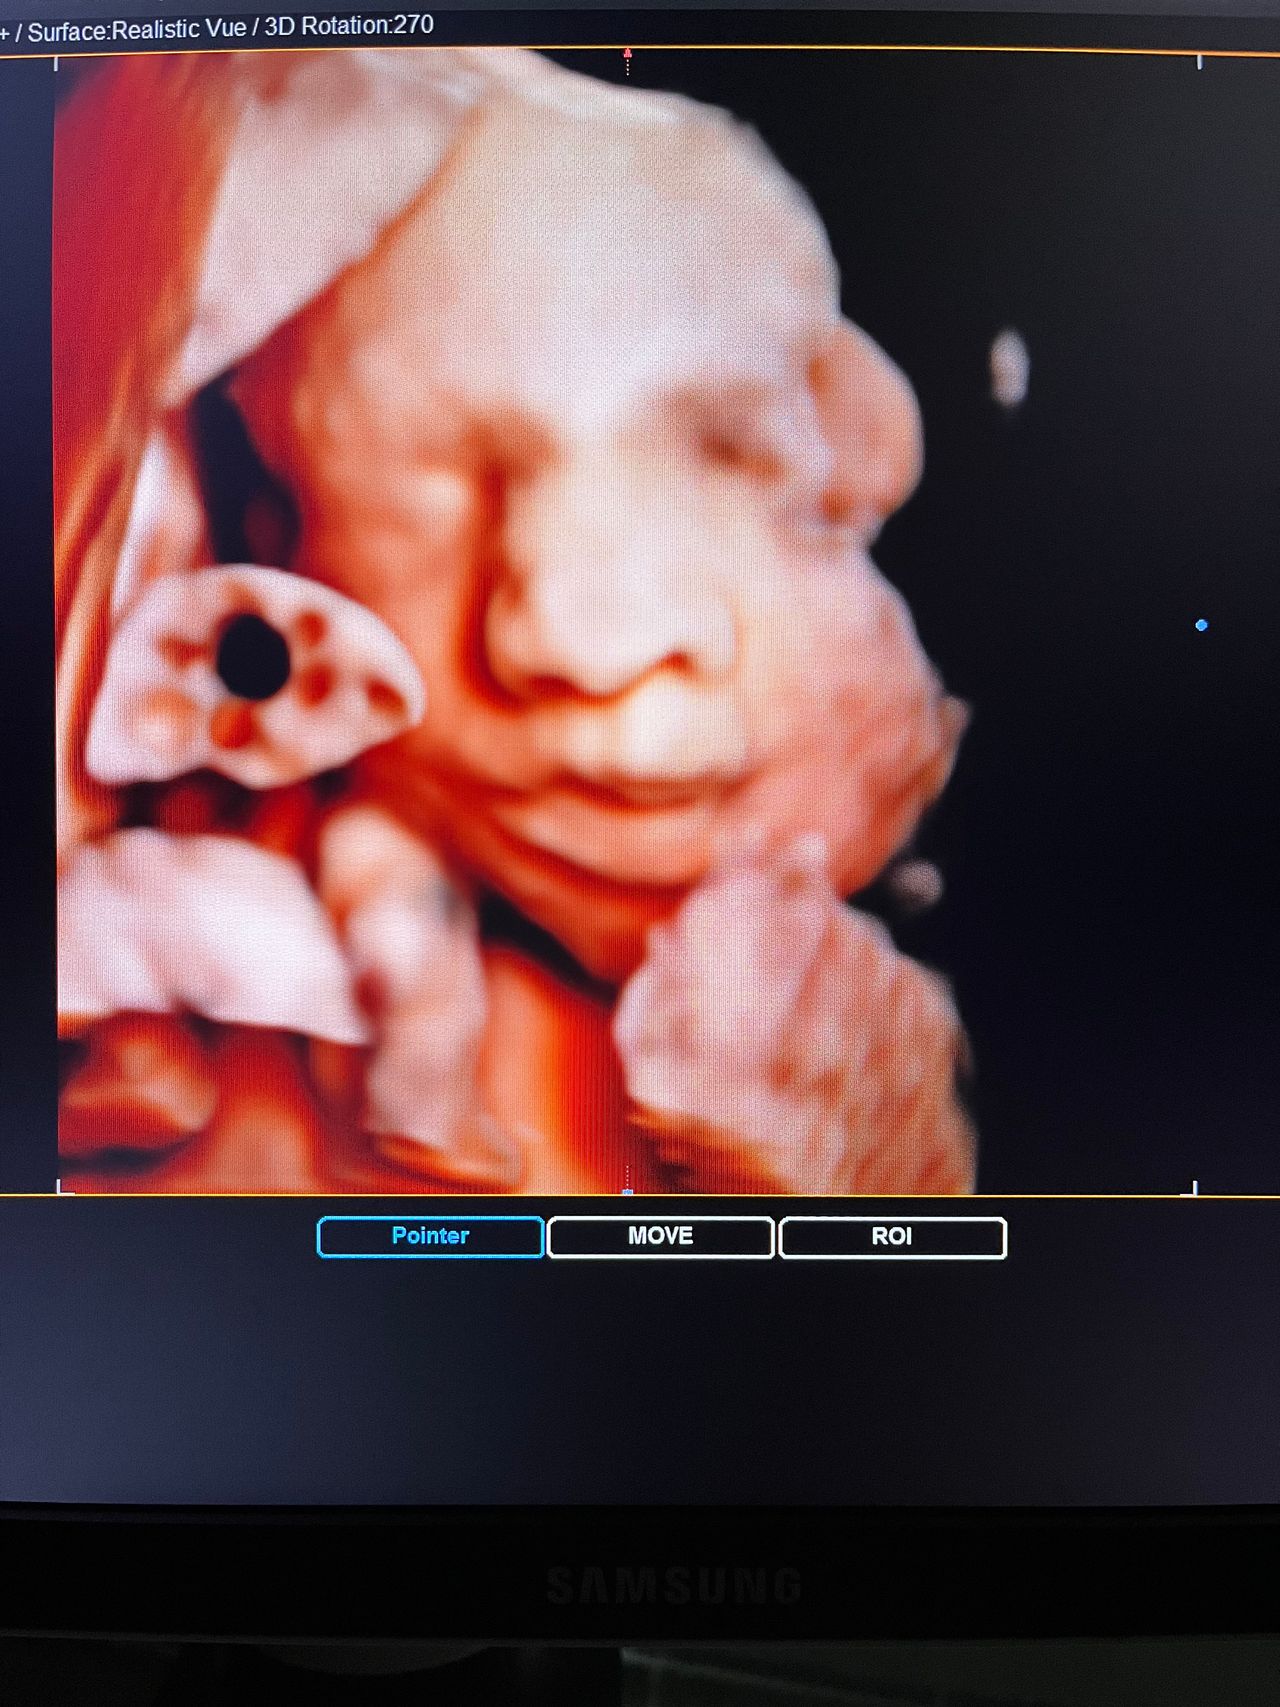

Attualmente lavoro come Dirigente medico nella SC di Ostetricia e Ginecologia dell'Ospedale Michele e Pietro Ferrero di Verduno, mi occupo prevalentemente di screening prenatale, ecografia ostetrica del I trimestre( misurazione translucenza nucale,NT), ecografia morfologica del II trimestre, ambulatorio pregresso taglio cesareo, ecografia ostetrica 3D. Seguo le gravidanze fisiologiche e quelle ad alto rischio , presto servizio in sala parto. Eseguo visite ginecologiche di I-II livello in regime ambulatoriale, counseling contraccettivo ed eventuale prescrizione pillola, inserimento spirale (IUD), dispositivo sottocutaneo (Nexplanon).

Foto e video